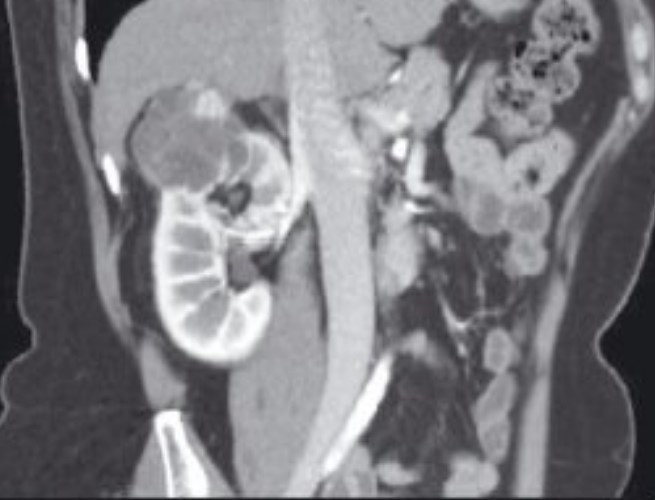

Интраренальная лоханка: рентгеновские снимки и примеры

Раздел: Фотоэссе